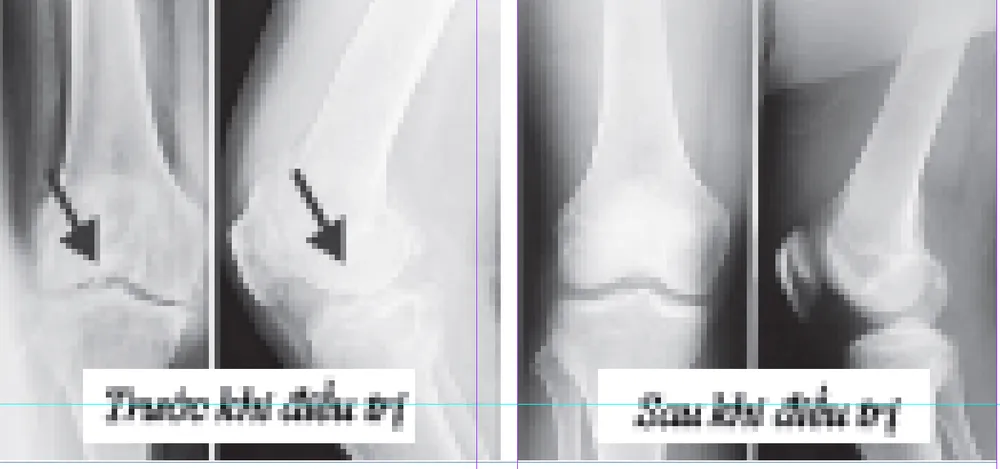

Đồng thời, điều tiết khí thận, thông qua dinh dưỡng của thận khôi phục xương khớp; thúc đẩy sự chuyển hóa của tổ chức sụn khớp, làm cho tế bào mới nhanh chóng thay thế tế bào cũ, khôi phục tổ chức sụn bị tổn thương, bảo vệ xương khớp lâu dài, khôi phục chức năng xương khớp, hỗ trợ chữa trị phong thấp xương khớp một cách triệt để. Ngoài ra, sản phẩm còn có tác dụng hỗ trợ chữa bệnh thoát vị đĩa đệm đốt sống lưng, tăng sinh xương đốt sống lưng, hẹp ống sống, viêm khớp, tăng sinh xương, viêm màng hoạt dịch, mềm hóa xương, tổn thương thấu kính mặt khum; các khớp sưng đau, tích nước, cứng lại, gập duỗi khó khăn. Bệnh nhân bị bệnh cột sống thắt lưng sau khi sử dụng sản phẩm sẽ khiến cho phần thoát vị bị mất nước và xẹp đi, loại bỏ các acid và các chứng đau nhức, tê, sưng, cứng. Chỉ cần một liệu trình sẽ giải phóng các rễ thần kinh bị chèn ép, lưng không còn đau và chân cũng không còn bị tê nữa, có thể dễ dàng khom lưng, đi lại bình thường; dùng 2 đến 3 liệu trình, hồi phục những bao xơ đã bị tổn thương, lúc này bệnh nhân hoàn toàn có thể chào tạm biệt bệnh cột sống thắt lưng.